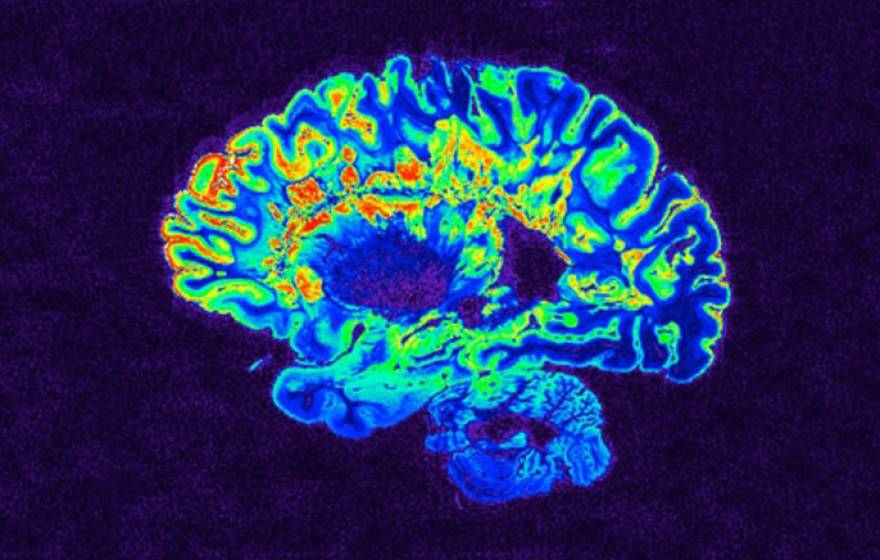

Over-the-counter allergy drug helps patients with chronic injury from multiple sclerosis

Clinical trial shows FDA-approved antihistamine restores nervous system function in MS patients.